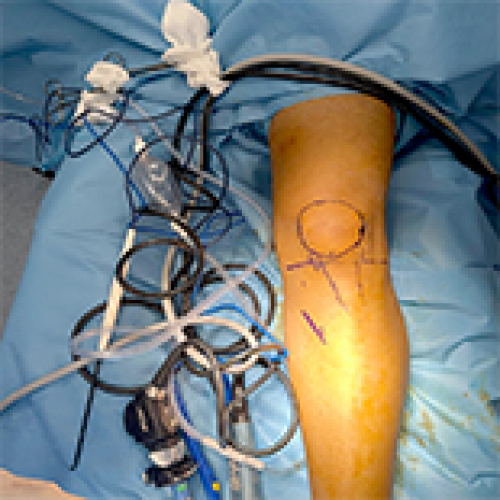

26 Oct 2024 : Clinical Research

Peroneus Longus vs Hamstring Tendon Autografts in ACL Reconstruction: A Comparative Study of 106 Patients’ Outcomes

DOI: 10.12659/MSM.945626

Med Sci Monit 2024; 30:e945626

Bilal Gök

, Muharrem Kanar

, Yılmaz Tutak

5,937